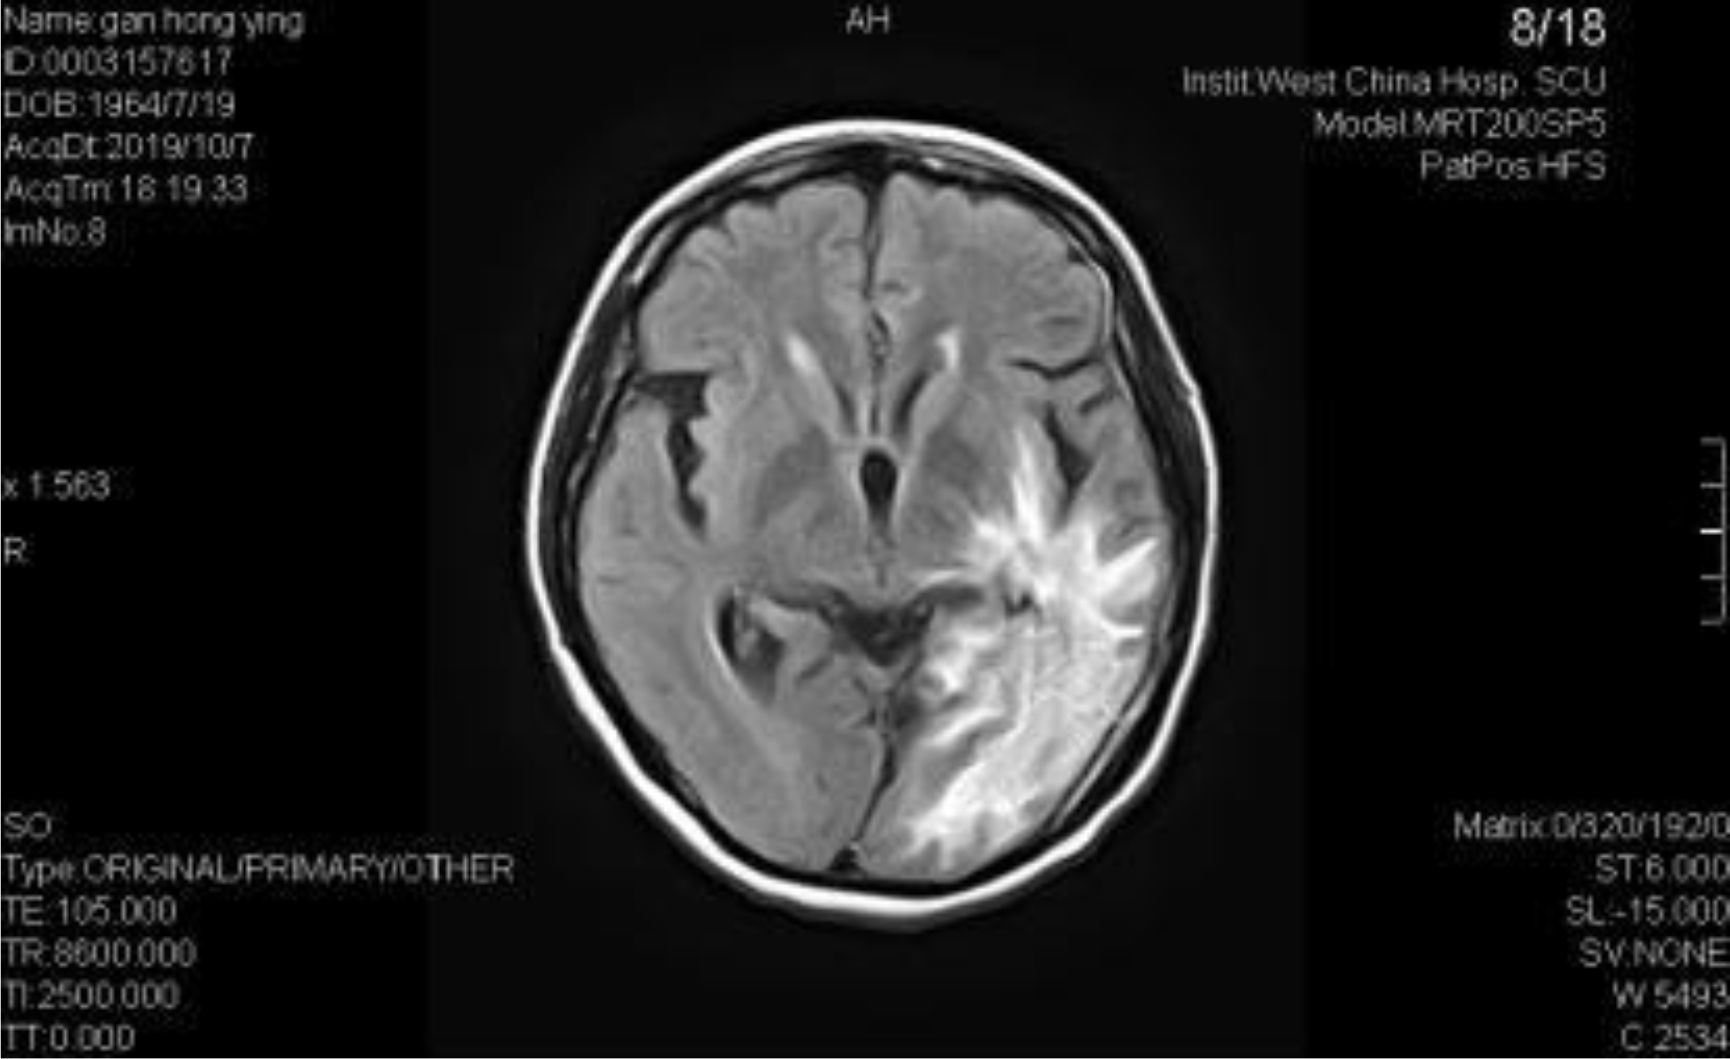

A 54-year-old female, developed a headache in December 2017. Examination showed that the left parietal occipital lobe occupied, and the first surgical treatment was performed, and the postoperative pathological diagnosis was glioblastoma. After operation, the patient received routine radiotherapy, 60Gy/33f, and temozolomide chemotherapy, 100mg/d (during radiotherapy), 300mg d1-5, q4w. In January 2019, the patient reexamined the MRI and found that the left temporal parietal space was occupied (Figure 1) and was operated again. The postoperative pathological diagnosis was still glioblastoma. The patient had occasional headache after operation, and the head MRI examination three months after operation indicated the progress of the disease (Figure 2). TTF was prepared to be used, and finally officially used the TTF treatment on July 4, 2019. The use time was relatively fixed, the utilization rate was 93%, and the compliance was good (Figure 3). During treatment, the patient developed allergic rash scattered on the scalp, mild itching, no ulceration and infection, and recovered quickly after topical application of antiallergic drugs. There had been several times that the patch temperature was too high, and the reasons are as follows: 1. The ambient temperature used was high (e. G. hot weather, direct sunlight, etc.). 2. The contact between the patch and the skin was not good. By instructing the patient to adjust the indoor temperature to about 24 °C, to use the headband or tape to strengthen the loose patch, to use the headband when sleeping at night, and to pay attention to clean the hair of the scalp every time, the situations had been significantly improved. Re-examination of the MRI in October 2019 showed that the condition was stable (Figure 4). Follow-up to 2020.1.23, the patient showed no symptoms of discomfort.

Figure 2